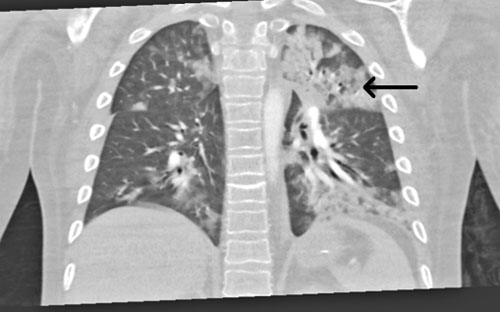

En uppföljande MR-undersökning av hjärnan visade multipla punktformiga förändringar med diffu­sionsinskränkning bilateralt i frontalloberna, parietalt och superiort i vänster occipitallob i vit substans, subkortikalt och kortikalt (Figur 3). Bilden bedömdes som fettembolisering. Vid eftergranskning av DT lungartär bedömdes de subsegmentella förändringarna i samtliga lunglober också som förenliga med fettembolisyndrom.

Figur 3. MR-undersökning av hjärna med punktformiga förändringar (vit pil) med diffusionsinskränkning.